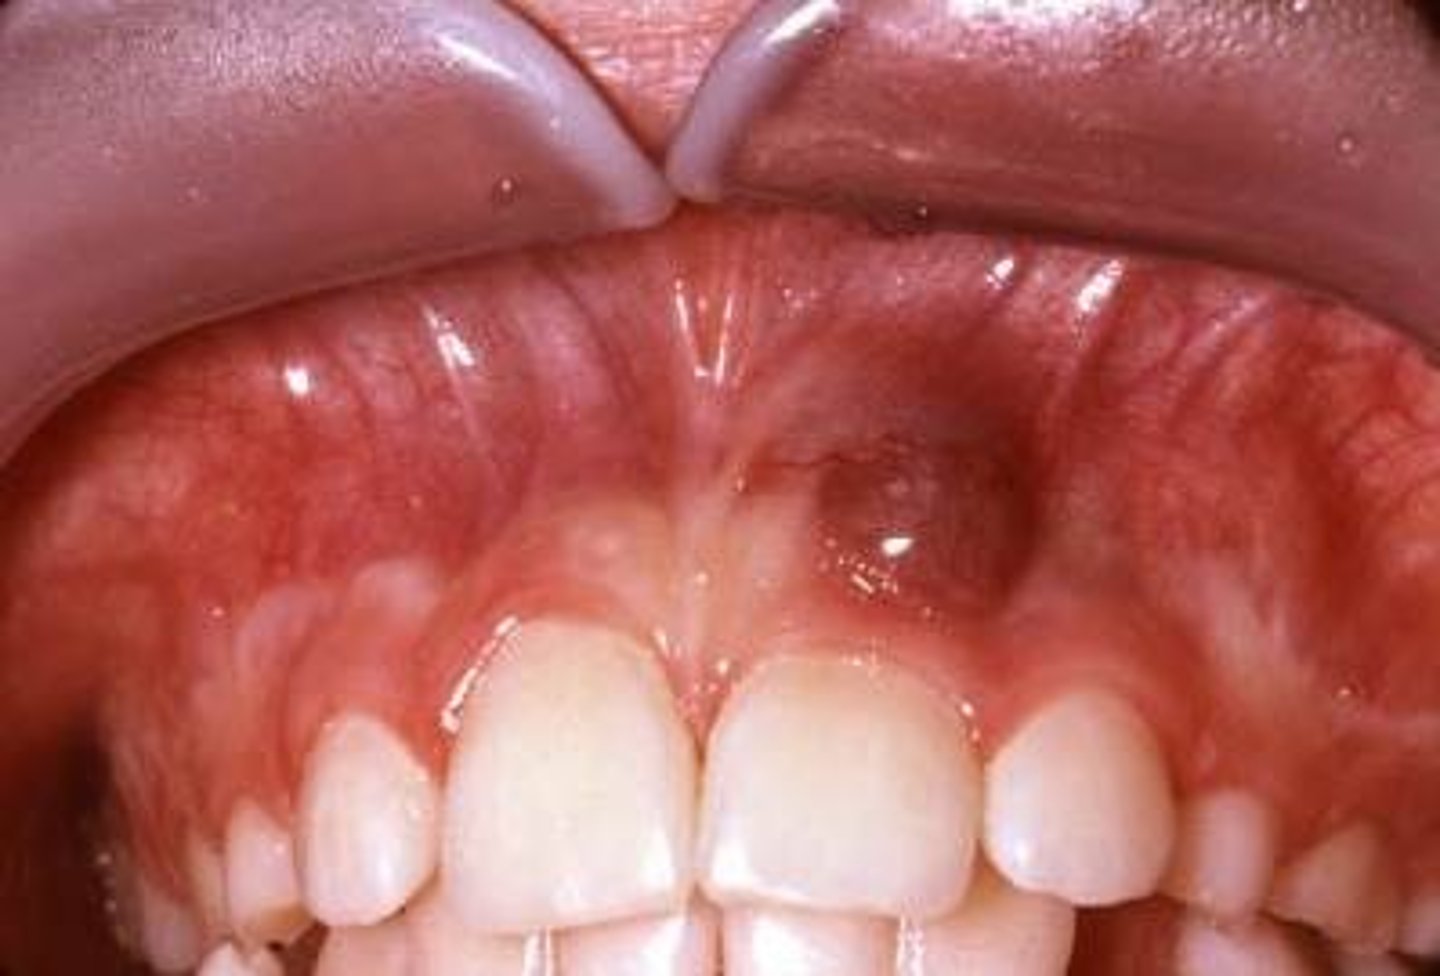

Eruption cyst

Soft tissue cyst surrounding the crown of an unerupted tooth.

Small, dome-shaped, translucent swelling filled with blood or serum and thus is red, brown, or blue-gray.